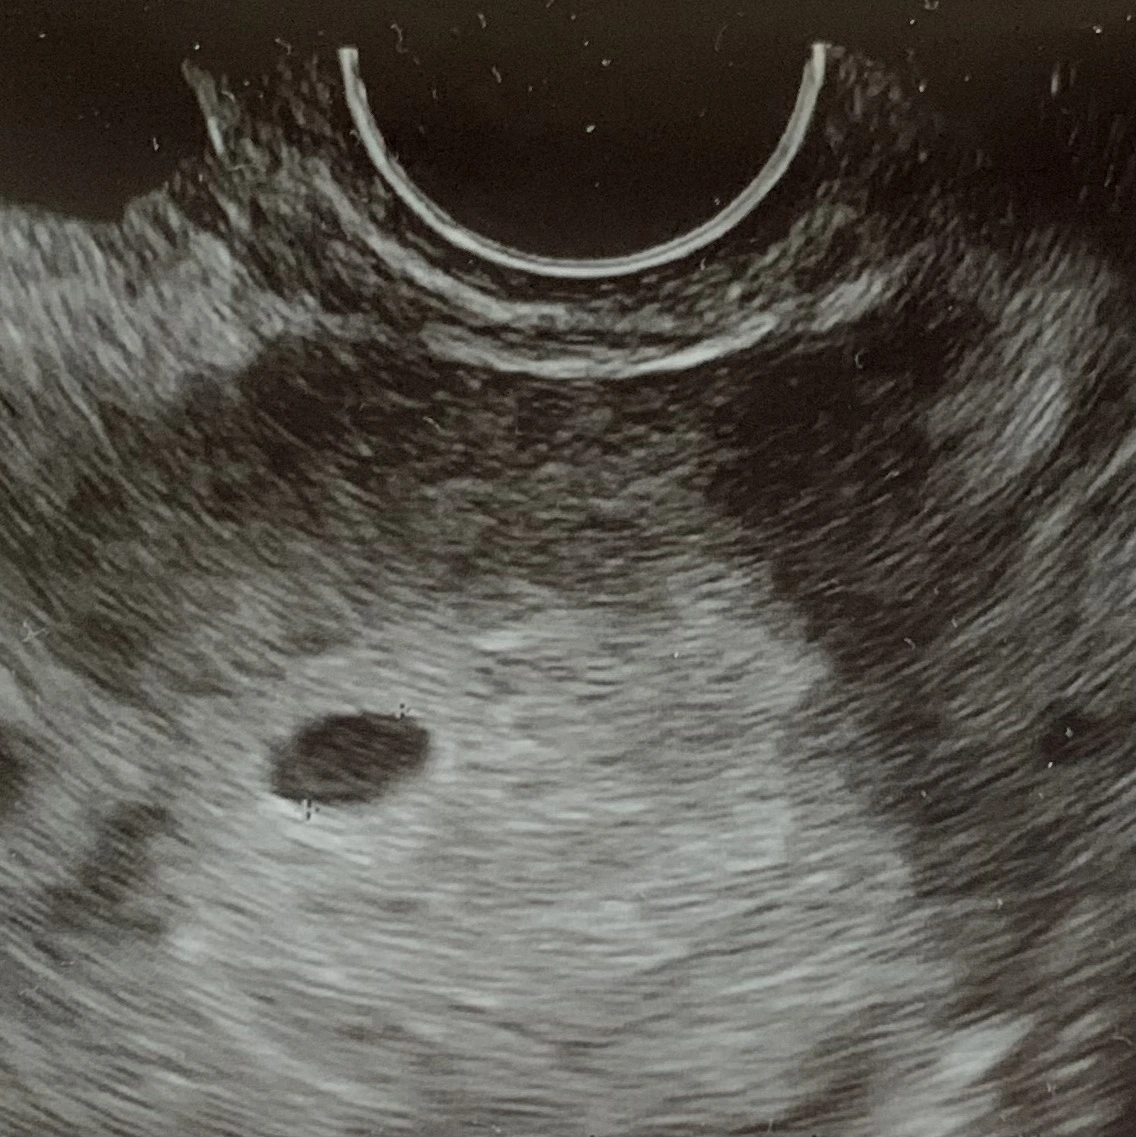

의사선생님을 만나 그간 벌어진 나의 상황을 이야기했고, 사진 찍어 두었던 또렷한 두 줄도 보여드렸다. 선생님과 나는 얼굴이 상기된 채 초음파를 시작했다. 어둑어둑하기만 하던 내 자궁에 동그라미 하나가 보였다. ‘아기집이 보이네요! 축하 드려요 임신이세요’ 산부인과 의자에 올려 둔 내 두다리의 힘이 스르륵 풀렸다. 내가 이렇게 많이 원했단 말인가 하는 생각이 들정도로 기뻤다. 2주 후에 약속을 잡고, 임신확인서와 산모수첩과 초음파사진을 들고 나왔다. 이 세상 아무도 아직 모르고 나랑 내 자궁 속 동그라미만 아는 기쁨이었다. 저녁에 퇴근한 남편에게도 우리의 동그라미를 소개했고 남편은 평소 눈물 많은 나도 안 흘린 눈물까지 찔끔거리며 기쁨에 동참했다.

IMG_5238 복사본.heic <언제 이렇게 집을 지어 놨는지, 거참!>